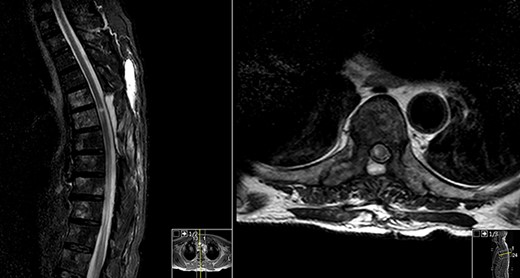

Postoperative MRI (Fig. 2) revealed a de novo T2 hyperintensity, possibly due to retraction of the thecal sac during surgery and consequently spinal cord lesion.

No hydrosyringomyelia or other complications were visible.